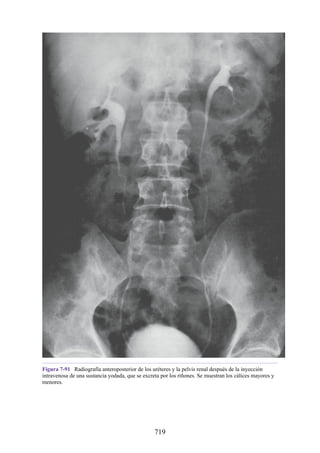

Notas clínicas

Lesiones ligamentosas